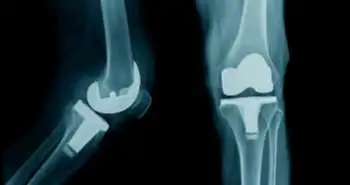

A study compared satisfaction results of staged & simultaneous bilateral TKA in OA patients

Elderly population across the world tends to suffer from osteoarthritis of the knees which could seriously affect their health and quality of life. Total knee arthroplasty (TKA) is a surgical procedure used to reduce pain and improve quality of life and function in patients when the disease progresses and becomes severe. Simultaneous bilateral TKA is an effective and safe approach for selected patients. The possibility of having different satisfaction levels between the first and second knee in the early stage after Shuai Huang et al. assessed simultaneous bilateral TKA.